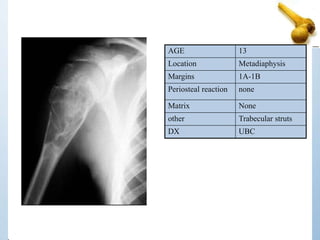

AGE 13

Location Metadiaphysis

Margins 1A-1B

Periosteal reaction none

Matrix None

other Trabecular struts

DX UBC